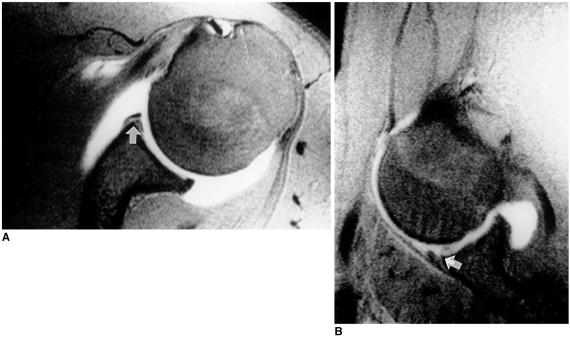

To compare, in terms of their demonstration of tears of the anterior glenoid labrum, oblique axial MR arthrography obtained with the patient's shoulder in the abduction and external rotation (ABER) position, with conventional axial MR arthrography obtained with the patient's arm in the neutral position.

MR arthrography of the shoulder, including additional oblique axial sequences with the patient in the ABER position, was performed in 30 patients with a clinical history of recurrent anterior shoulder dislocation. The degree of anterior glenoid labral tear or defect was evaluated in both the conventional axial and the ABER position by two radiologists. Decisions were reached by consensus, and a three-point scale was used: grade 1=normal; grade 2=probable tear, diagnosed when subtle increased signal intensity in the labrum was apparent; grade 3=definite tear/defect, when a contrast material-filled gap between the labrum and the glenoid rim or deficient labrum was present. The scores for each imaging sequence were averaged and to compare conventional axial and ABER position scans, Student's t test was performed.

In 21 (70%) of 30 patients, the same degree of anterior instability was revealed by both imaging sequences. Eight (27%) had a lower grade in the axial position than in the ABER position, while one (3%) had a higher grade in the axial position. Three whose axial scan was grade 1 showed only equivocal evidence of tearing, but their ABER-position scan, in which a contrast material-filled gap between the labrum and the glenoid rim was present, was grade 3. The average grade was 2.5 (SD=0.73) for axial scans and 2.8 (SD=0.46) for the ABER position. The difference between axial and ABER-position scans was statistically significant (p<0.05).

MR arthrography with the patient's shoulder in the ABER position is more efficient than conventional axial scanning in revealing the degree of tear or defect of the anterior glenoid labrum. When equivocal features are seen at conventional axial MR arthrography, oblique axial imaging in the ABER position is helpful.